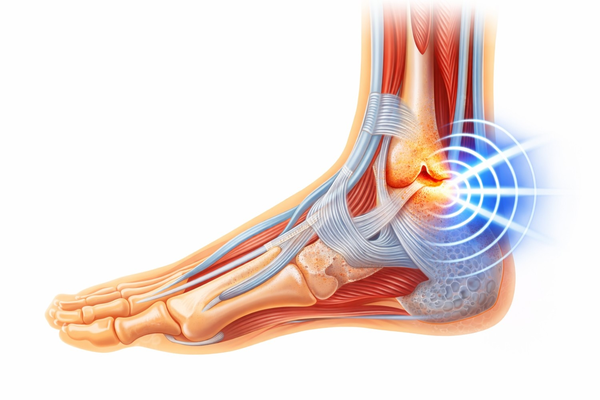

Therapy That Comes to You

Our mobile clinic delivers advanced pain relief and rehabilitation at your doorstep. Get high‑quality care wherever you are.